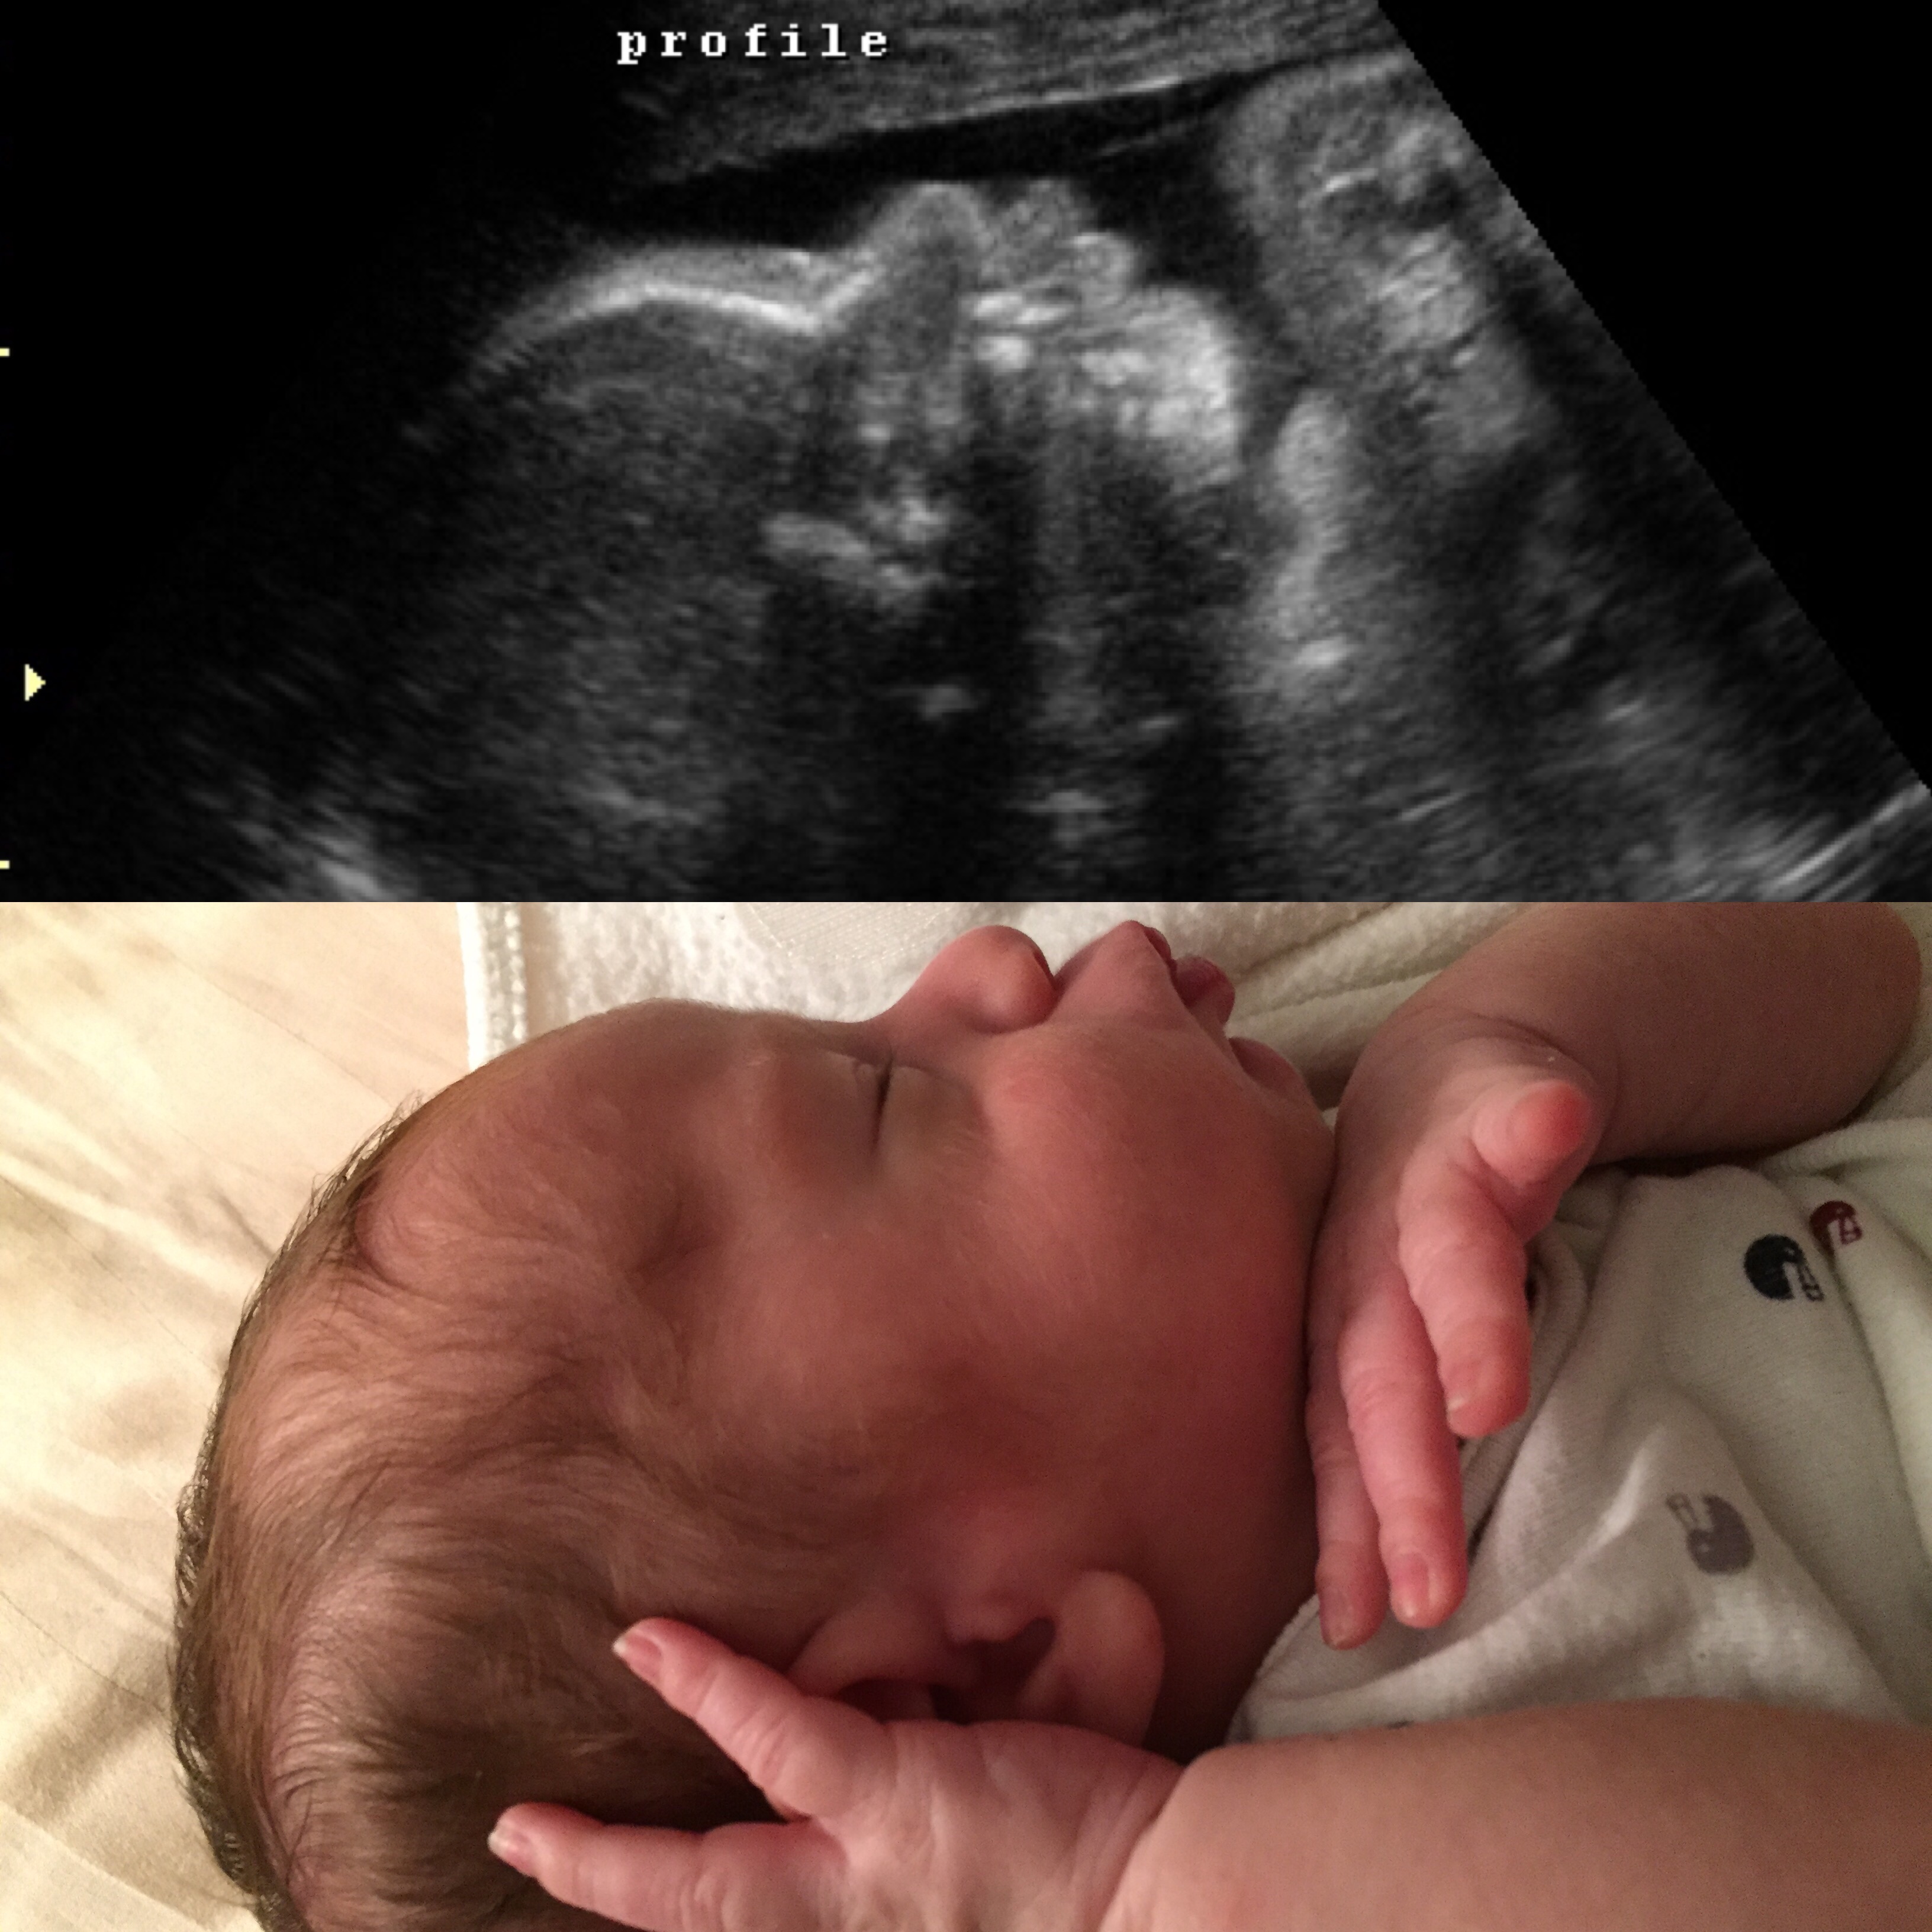

Introducing...

Caspian James EDD 10/20/15 born 10/15/15 at 1:32pm 6 lbs, 6 oz, 19.29" in

On 10/15 I started feeling regular contractions around 4am, not crazy intense yet but still painful and ~15 mins apart. They got closer to 12 mins apart by 6am. I wasn't scheduled for my c-section (due to breech presentation) until 10/19, so I called the doctor's office at 8:30am and they sent me to L&D to get checked out. I hadn't had cervical checks done at my OB so they hooked me up to the monitor and did a couple of checks an hour or so apart. After confirming I was in early labor and dilating (went from 2cm to 3cm within the hour), the doctor on-call decided that we'd be having the baby that day!! There was no point in waiting, especially since contractions were getting more uncomfortable and I was dilating. I got prepped for surgery, and by 1pm was in the OR. This was my first surgery ever, and while it was a bit scary feeling 85% of my body all numb, the sensations and uncomfortable pressure, it all went smoothly. They spent a bit of time on pulling the baby out since he was apparently so wedged in. No wonder he couldn't flip! He really had no room in my heart-shaped uterus inside my tiny body. Thankfully he was perfectly healthy. He also latched on and took to breastfeeding right away. He's a breastfeeding champ.

Everything happened so fast but it was worth it in the end. We're so in love with our little Caspian!

I'm currently 3 weeks post-partum and loving every moment of this new journey. The newborn phase is challenging, but the endless cycles of sleep-deprived feedings and diaper changes are so worth it when I look at this little face. As far as my c-section recovery, the first week or so was really tough even with pain meds. It's hard to get around and take care of a newborn when your core is wiped out AND you're recovering from major abdominal surgery. Thankfully my husband has been so helpful and is already such a great dad to Caspian. After I got through the first week, I felt a lot closer to normal and have been feeling great ever since. Incision has healed nicely and I'm looking forward to being cleared for exercise in a few weeks. For now, I'm taking it easy and enjoying every minute of bonding with our little one.